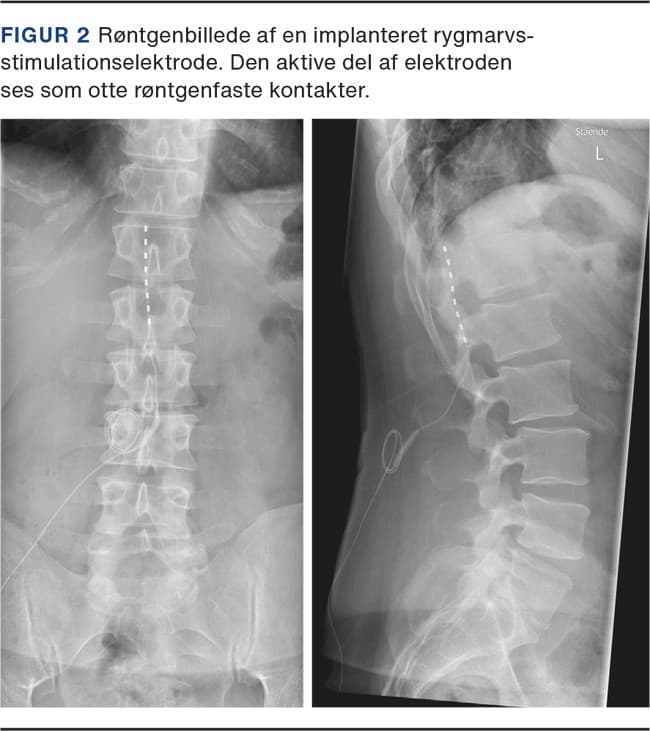

SCS er den mest udbredte invasive neuromodulationsbehandling for smerter, både i Danmark og globalt. Behandlingsprincippet er elektrisk stimulation af rygmarvens bagerste, hvide substans (bagstrengen) via 1-2 elektroder (i særlige tilfælde op til fire) permanent implanteret i epiduralrummet [17] (Figur 1 og Figur 2).

Elektroden implanteres typisk ved et mindre kirurgisk indgreb i sedation; i nogle tilfælde vælges en såkaldt pladeelektrode implanteret via en hemilaminektomi i generel anæstesi. Korrekt placeret skal elektrodens elektriske felt fremkalde en summende fornemmelse i det smertevoldende område, men nyere stimulationsparadigmer (burst og HF10) har vist, at selve den bevidste opfattelse af disse paræstesier ikke er en forudsætning for behandlingsresultatet [18].

Virkningsmekanismen er endnu ikke fuldt afklaret, men er formentlig både på segmentalt/spinalt og cerebralt niveau [19, 20].